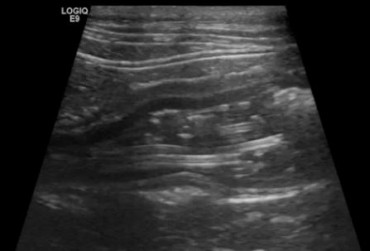

Określenie „rozpoznanie cioci Minnie” pochodzi ze Stanów Zjednoczonych i jest żartobliwym określeniem rozpoznania patognomonicznego, stosowanym głównie przez radiologów. Zwrot ten stał się popularny w latach 90. XX w. za sprawą strony internetowej o takim tytule. Obecnie to określenie stosuje się również w metodologii nauczania klinicznego. W artykule przedstawiono przypadki rozpoznań „cioci Minnie” z własnego archiwum ultrasonografii jamy brzusznej małych zwierząt.